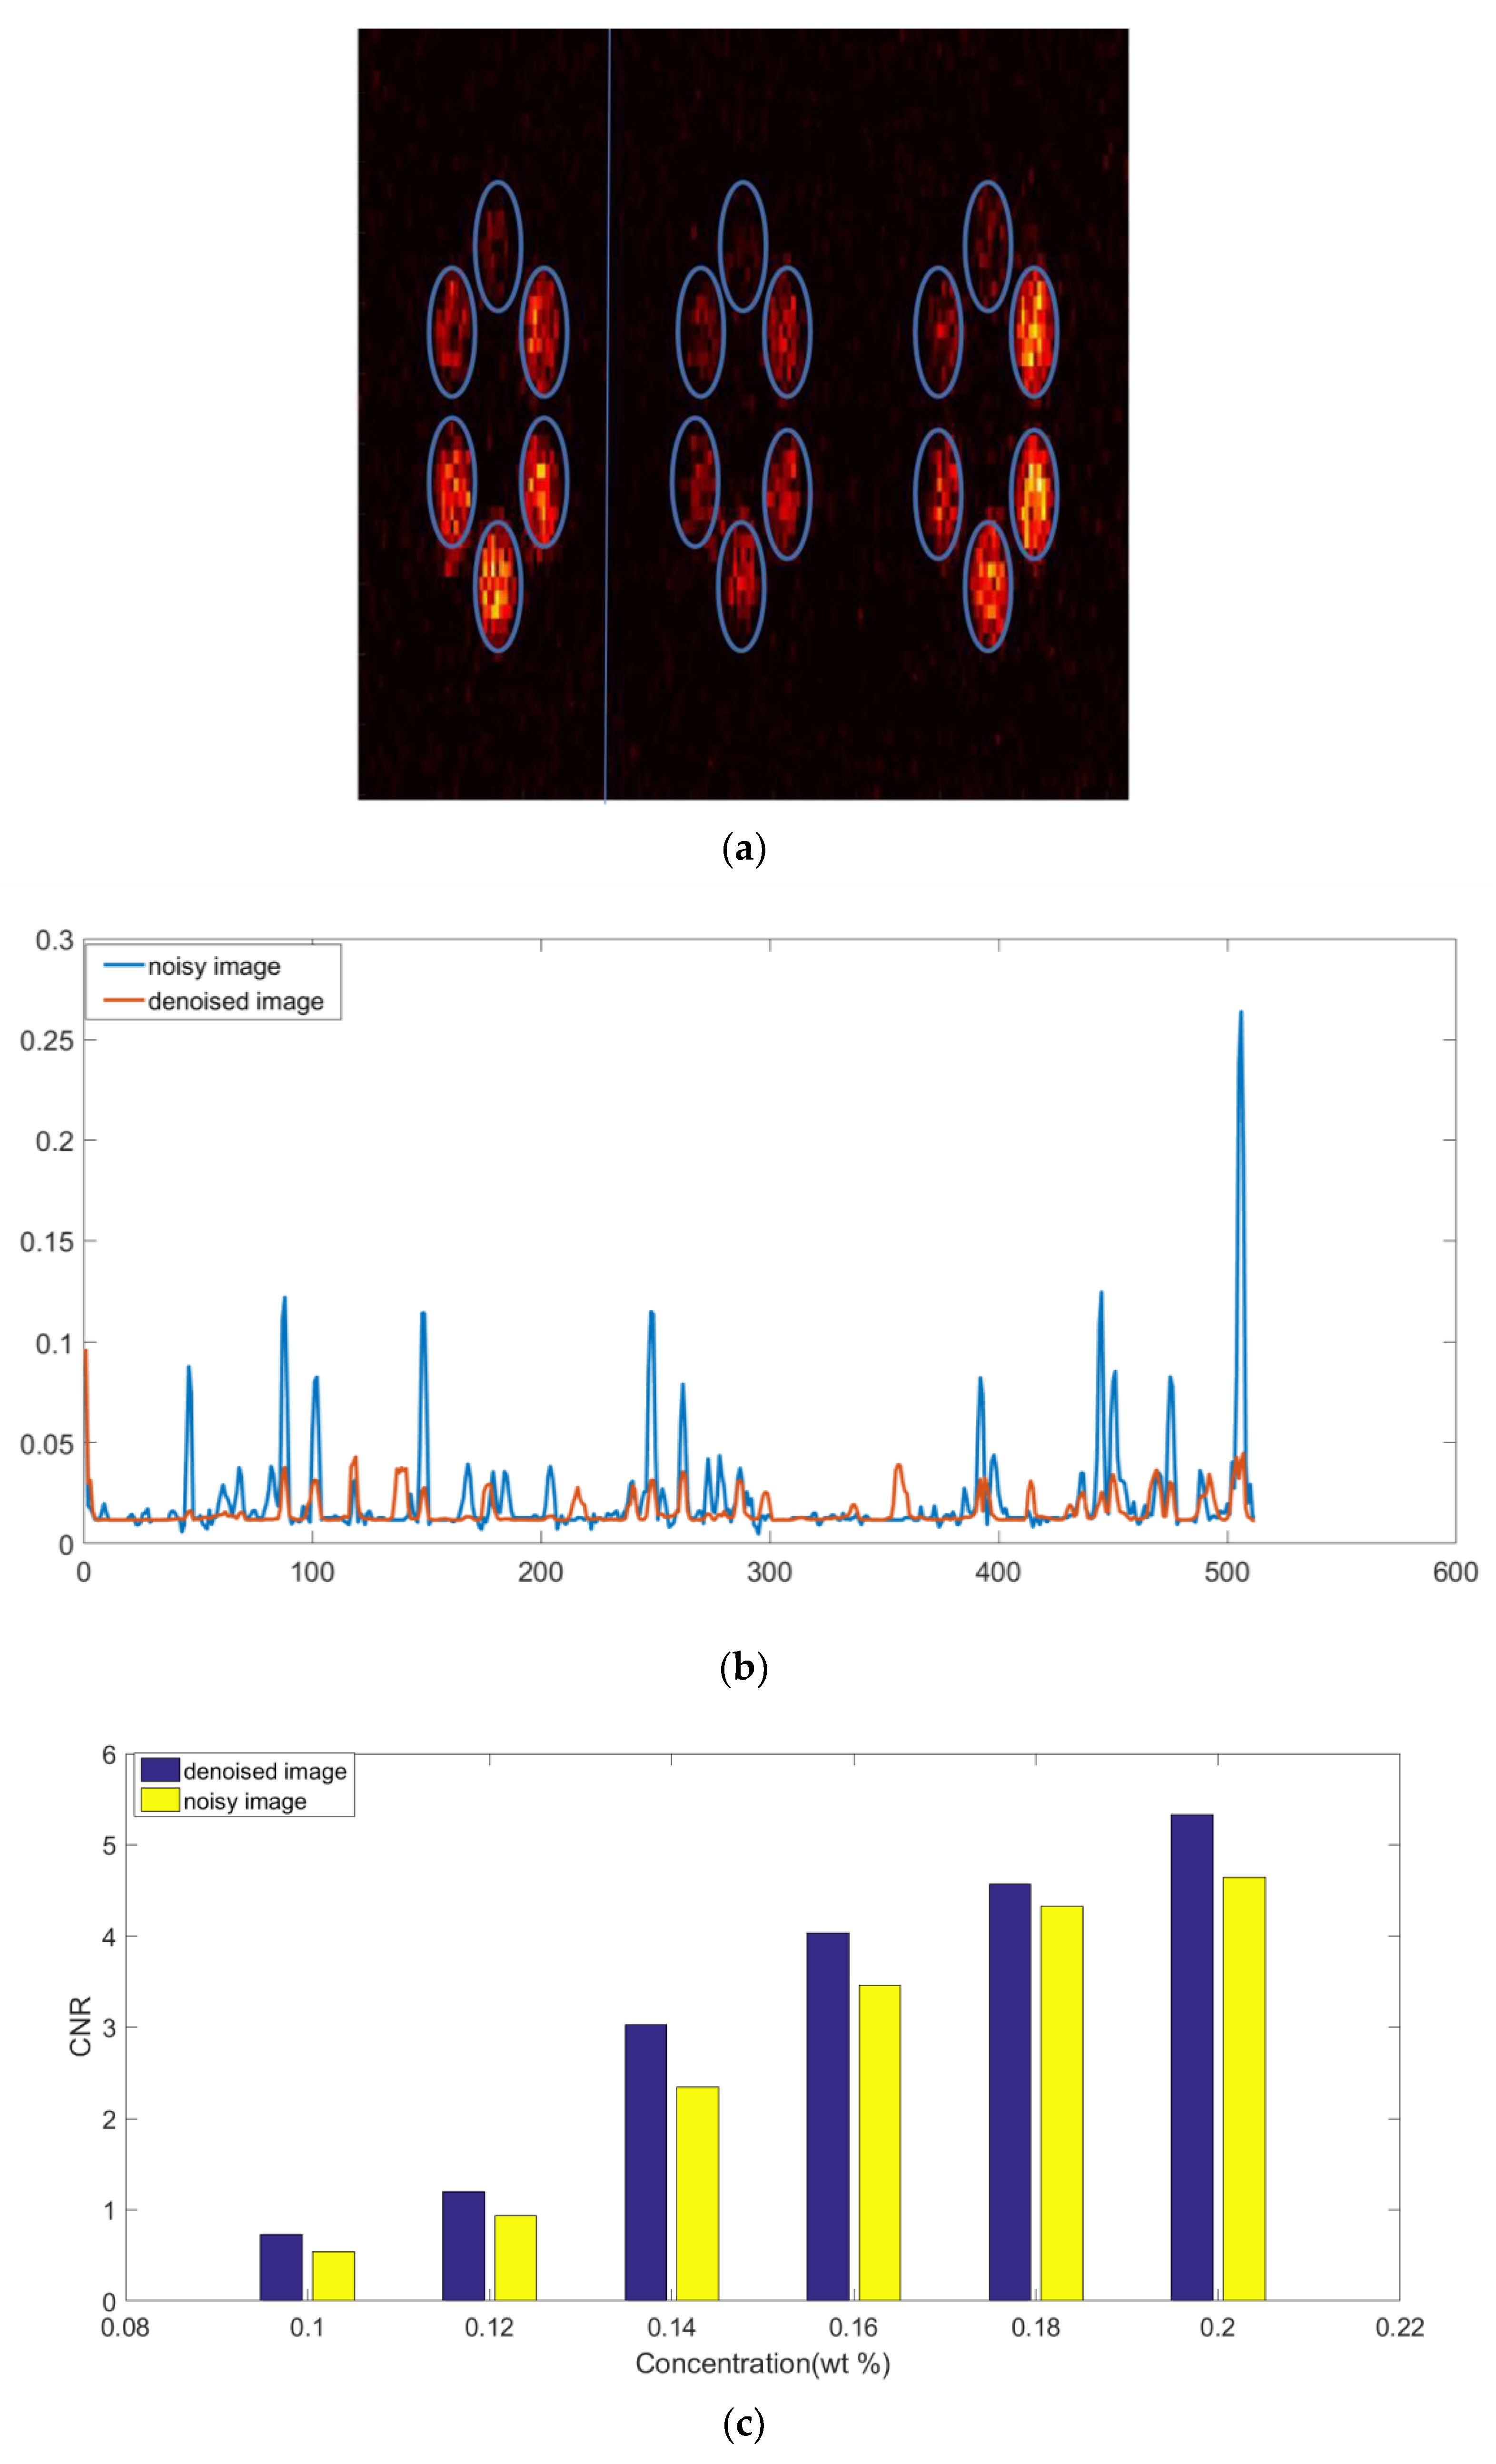

3. Results

4. Discussion